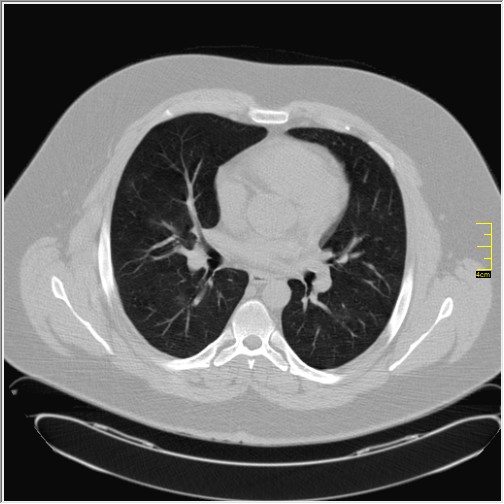

Foto: Aleksandar Ivković Foto: Aleksandar Ivković Foto: Aleksandar Ivković Strašna razlika kod pluća pušača i kovid pozitivne osobe autor: Božica Luković Zdravlje 23. jan. 2021. 12:06 > 23. jan. 2021. 12:15 0 Podeli vest: Radiolog Aleksandar Ivković od početka pandemije daje korisne informacije o svim aspektima kovida 19. On je nedavno uporedio rendgen snimke pluća zdrave osobe, pušača, osobe koja je zaražena gripom H1N1, a onda i osobe koja ima kovid 19. Razlike su zapanjujuće. Podeli vest: Oglas Objavu doktora Ivkovića sa njegovog bloga "Ljudi i ostale laži" prenosimo u celosti."Nedavno sam video u medijima da je neko preneo rdg sliku i razlike kod nalaza zdrave osobe, pušača i bolesnog od kovida 19. Kako nisam baš previše zadovoljan onim što je prikazano, evo kako to izgleda u našoj varijanti. Zdrava osoba CT nalaz kod zdrave osobe podrazumeva da ne postoje nikakvi poremećaji strukture plućnog parenhima, da su krvni sudovi uredni i da nema suženja disajnih puteva, kao i da nema uvećanih limfnih žlezda u hilusima pluća i medijastinumu. Foto: Aleksandar Ivković | Foto: Aleksandar Ivković * Foto: Aleksandar Ivković | Foto: Aleksandar Ivković Zdrava muška osoba mesec dana nakon zapaljenja pluća tokom kovida 19. Nalaz bez nekih posebnih problema iako se naziru tragovi zapaljenja. Snimak u boji je zdrava osoba, nepušač, bez ikakvih bolesti pluća u istoriji. Grip H1N1 Pokazaću samo drastične nalaze kod gripa H1N1, to je znači onaj grip koji je izazvao epidemiju španske groznice i epidemiju 2009. godine koja još uvek nije prestala (svake godine imamo makar 15%). Foto: Aleksandar Ivković | Foto: Aleksandar Ivković * Foto: Aleksandar Ivković | Foto: Aleksandar Ivković * Foto: Aleksandar Ivković | Foto: Aleksandar Ivković * Foto: Aleksandar Ivković | Foto: Aleksandar Ivković Nisu svi pacijenti imali ovakve nalaze, pokazujem one koji su imali tešku kliničku sliku. Kod gripa se sve odvija obično u sedam dana. Kao što se vidi, zapaljenje je bilo jednostrano, uglavnom. Ali kada je dolazilo do pogoršanja, onda je centralno obostrano dolazilo do edema pluća. Pušenje Kod pušača postoje razne varijante nalaza na plućima. U principu nisu tako dramatične kao što su zapaljenja. Nalaz na plućima kod pušača može biti potpuno normalan. Ovo ne pišem zato što podržavam pušenje, naprotiv, veliki sam protivnik, ali iznošenje laži nikada nije dobro. Dve dijagnoze su bitne kao posledica pušenja. Prva je hronična plućna opstruktivna bolest: Foto: Aleksandar Ivković | Foto: Aleksandar Ivković * Foto: Aleksandar Ivković | Foto: Aleksandar Ivković * Foto: Aleksandar Ivković | Foto: Aleksandar Ivković Jasna je razlika u nalazu, posebno na ovim slikama u boji, gde su ta plava polja delovi pluća koji su propali zbog cigareta (može da se uporedi sa zdravim plućima iznad).Druga bolest koja je česta kod pušača je u svakom slučaju karcinom. Foto: Aleksandar Ivković | Foto: Aleksandar Ivković * Foto: Aleksandar Ivković | Foto: Aleksandar Ivković * Foto: Aleksandar Ivković | Foto: Aleksandar Ivković * Foto: Aleksandar Ivković | Foto: Aleksandar Ivković Tkivo koje raste unutar pluća i razjeda ga. Takav je nalaz kod karcinoma pluća. Često je uzrok upotreba cigareta. Kovid 19 O kovidu sam pisao puno puta. Evo nekih slika, radi poređenja. Foto: Aleksandar Ivković | Foto: Aleksandar Ivković * Foto: Aleksandar Ivković | Foto: Aleksandar Ivković * Foto: Aleksandar Ivković | Foto: Aleksandar Ivković * Foto: Aleksandar Ivković | Foto: Aleksandar Ivković Nakon što pacijent bude izlečen od gripa ili kovida 19, pluća se mogu vratiti u normalu.To je razlika u odnosu na posledice upotrebe cigareta. Ovi snimci nisu postavljeni da bi se poredile bolesti, već da bi se ukazalo kako različite bolesti deluju na pluća. I ono što je veoma važno, ako neko dobije jednu od ovih bolesti, ne znači da u toku života neće dobiti drugu.Ne pišem zato smo smatram da sam najpametniji ili najpozvaniji da objašnjavam, nisam kao neki pojedinci ubeđen da samo ja imam znanje i istinu, pišem jer drugi ćute. Pišem jer ima i puno onih koji iznose laži, mora se tome stati na put.A ovi, koji pišu da sam umro, da sam oboleo od karcinoma, ovi koji mi žele da nađem dobro grobno mesto, šta da vam kažem, vi ste mi inspiracija. Svesni ste da sam u pravu i odlično znam da ste već uradili sve da se vakcinišete i mnogi od vas će to uraditi pre mene ali i dalje ćete ubeđivati druge da se ne vakcinišu i da je dobro za njih da se razbole i umru. Ima puno reči za vas u svim našim slovenskim jezicima, znate vi sami šta ste", piše dr Ivković.***Bonus video:https://youtu.be/MWucTT0qBsIPratite nas i na društvenim mrežama:FacebookTwitterInstagram Dr Lukić otkrio spisak svih antibiotika za kovid upalu pluća Zdravlje 0 Dr Žujović: Kako oporaviti pluća posle korone Zdravlje 0 Pet znakova da ti je kovid zahvatio pluća Zdravlje 0 Virusolog Ana Banko ruši veliku zabludu o ruskoj vakcini Emisije 0 aleksandar ivković korona kovid pluća snimak pluća Pratite nas na društvenim mrežama: Koje je tvoje mišljenje o ovoj temi? Učestvuj u diskusiji ili pročitaj komentare Budite prvi koji će ostaviti komentar Pošalji komentar Pročitaj komentare (0)